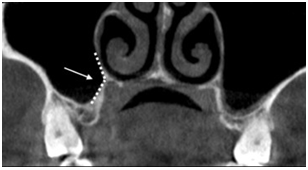

Se ha observado que la morfología del seno posee un papel muy importante en el procedimiento de elevación de seno. Cho et al. (36), refieren que el ángulo entre las paredes alveolares bucal y palatina definido como ángulo A, está relacionado con el riesgo de perforación. Siendo las zonas de los premolares las que presentan ángulos más agudos por lo que el riesgo de perforación en esa área es más elevado. Otro de los ángulos formados que presentaría mayor dificultad durante la elevación de seno, incrementando el riesgo de perforar la membrana, es el formado por el proceso nasopalatino (PNP) descrito inicialmente por Chan et al. (37). (Fig. 3) Este consta de una intersección de dos líneas imaginarias correspondientes a la zona más baja de la pared lateronasal y a la pared del paladar del seno maxilar. En una revisión sistemática se demostró que el PNP se ubicó más cerca al reborde crestal en la zona de molares que en premolares, dando como resultado un ángulo más obtuso en zona de molares, permitiendo una zona de mayor acceso. Por otro lado, el PNP presentó un ángulo agudo en las zonas de premolares lo que dificultaría la elevación de la membrana en esa área y está presente en un 15%. Asimismo, se refiere que esto podría aumentar la tensión en la membrana lo que a su vez se ve reflejado en un incremento de la incidencia de perforación a ese nivel. Niu et al. (38), presentaron un nuevo sistema de clasificación, donde describen características clínicas y de distribución de contornos. Hicieron una división de 5 tipos de contorno de seno maxilar en una imagen coronal que abarca las paredes palatina y bucal: tipo A estrecho-cónico, tipo B cónico, tipo C ovoide, tipo D cuadrado, tipo E irregular. Además, para cada tipo se describieron subtipos, los 4 primeros tipos compartían los siguientes subtipos: subtipo 1 cuando no hay presencia de proceso palatino- bucal, subtipo 2 cuando hay presencia de proceso palatino-bucal, subtipo 3 cuando hay presencia de proceso palatino-nasal. Para el quinto tipo, el tipo E, se describieron los siguientes subtipos: subtipo 1 si la raíz del diente se introducía dentro del seno, subtipo 2 si el piso del seno era irregular, y subtipo 3 si poseía septum o exostosis en el piso de seno. Esta clasificación permitiría un análisis ordenado de la morfología del seno y la consiguiente toma de decisiones en el plan de tratamiento.